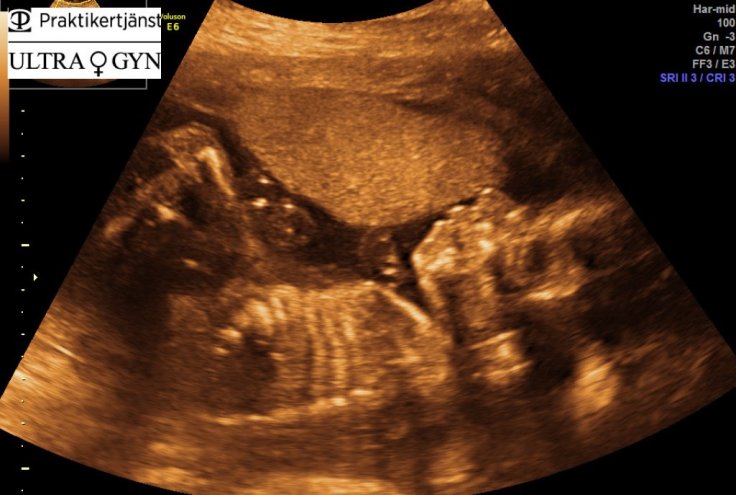

Till skillnad från förra gången då det vimlade av folk inne i salen så var de bara sex-sju stycken runt mig. Ingen jäktade och de förklarade hela tiden vad de gjorde och varför. Ryggmärgsbedövningen som jag var lite nervös inför gick superbra, bedövningssprutan kändes mer än själva ryggmärgssprutan och inom ett par sekunder så tappade jag känseln i underkroppen, ungefär upp till brösten, och de ”välte” ner mig på operationsbordet.

Ett skynke sattes upp framför mig, nedanför midjan och de började med snittet.